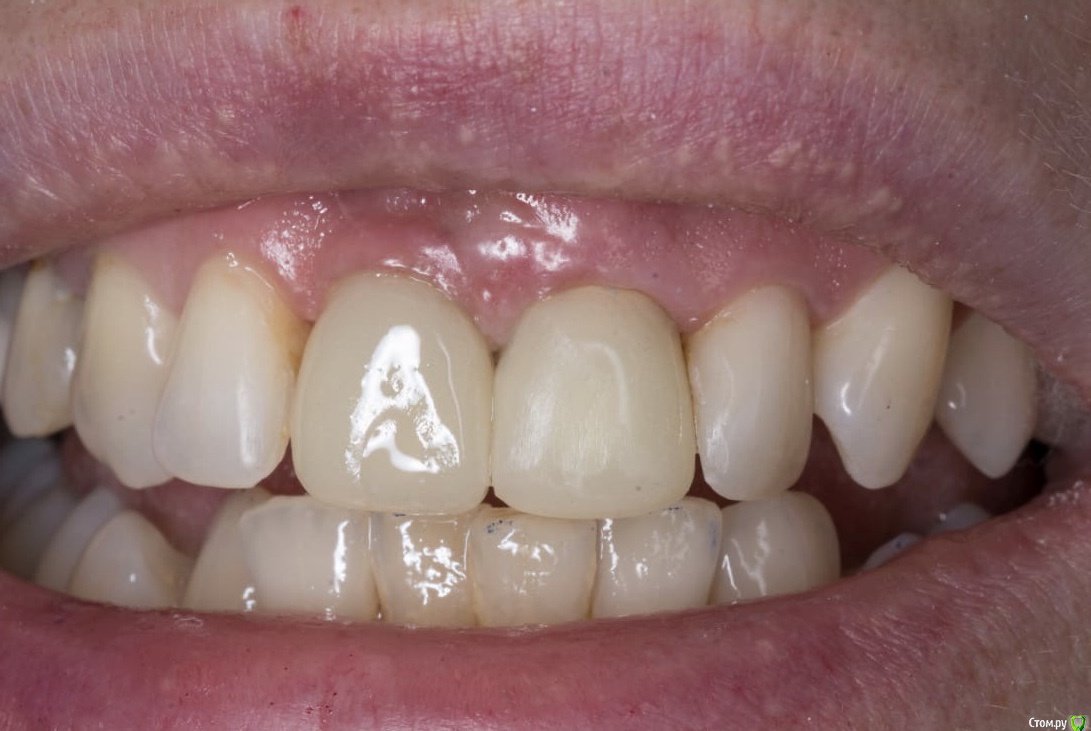

Александр07 Опубликовано 2 мая, 2020 Поделиться Опубликовано 2 мая, 2020 Коллеги доброго дня Обратилась молодая пациентка , в районе 30, десневая улыбка, планируется пластика во фронте с целью увеличения высоты сосочков, ну и объём можно немного добавить1.1 импл, сосочек 2.1-2.2 тоже ушёл от предыдущих операций, Раздумываю какой метод выбрать, есть несколько вариантовСклоняюсь к методу по Цуру - создание туннеля и подтянуть транс швами за межзубные контакты Вторым вариантом методика Сузуки но объём тогда вестибулярно не затронемИ по Зукелли , но опасаюсь осложнений в виде рубцов и т д, Кто что посоветует) Ссылка на комментарий

kramer Опубликовано 2 мая, 2020 Поделиться Опубликовано 2 мая, 2020 Сделал бы более протяженный контакт между 11 и 21 Ссылка на комментарий

Aquarius Опубликовано 2 мая, 2020 Поделиться Опубликовано 2 мая, 2020 (изменено) Я за Масану. И контакт на 21 надо изменить Изменено 2 мая, 2020 пользователем Aquarius Ссылка на комментарий

krokomot Опубликовано 2 мая, 2020 Поделиться Опубликовано 2 мая, 2020 нужна другая форма коронок, может и пластика не потребуется 2 Ссылка на комментарий

krokomot Опубликовано 2 мая, 2020 Поделиться Опубликовано 2 мая, 2020 проблема центрального сосочка в коронке 2.1. нудно переделать коронку 2.1 и 1.1, потом думать о пластиках. Ссылка на комментарий

Irouil Опубликовано 2 мая, 2020 Поделиться Опубликовано 2 мая, 2020 Я тоже не вижу, что тут еще давить. У коронки плохой контур в пришеечной части, но ближе к платформе винта коронка должна быть тоньше с таким рентгеном, значит там поддержка тканей еще уменьшится. Судя по оклюзионному снимку в оро-вестибулярном направлении коронке не хватает объёма, зенит тоже апикальнее необходимого. Надо разобраться с соседней 1-кой, если замена там коронки - вариант, то можно рассмотреть апикализацию зенита на зубе на 1 мм в итоге. Но, имхо, без хирургии тут не выйдет ничего Ссылка на комментарий